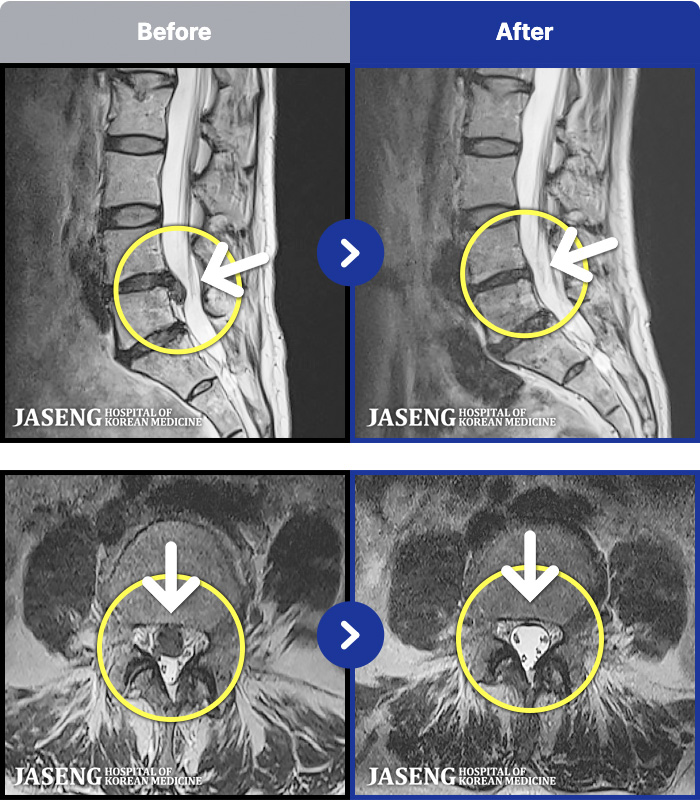

1,297 MRI ũ ʸ Ȯϼ.

[] 23.11.11~25.06.04